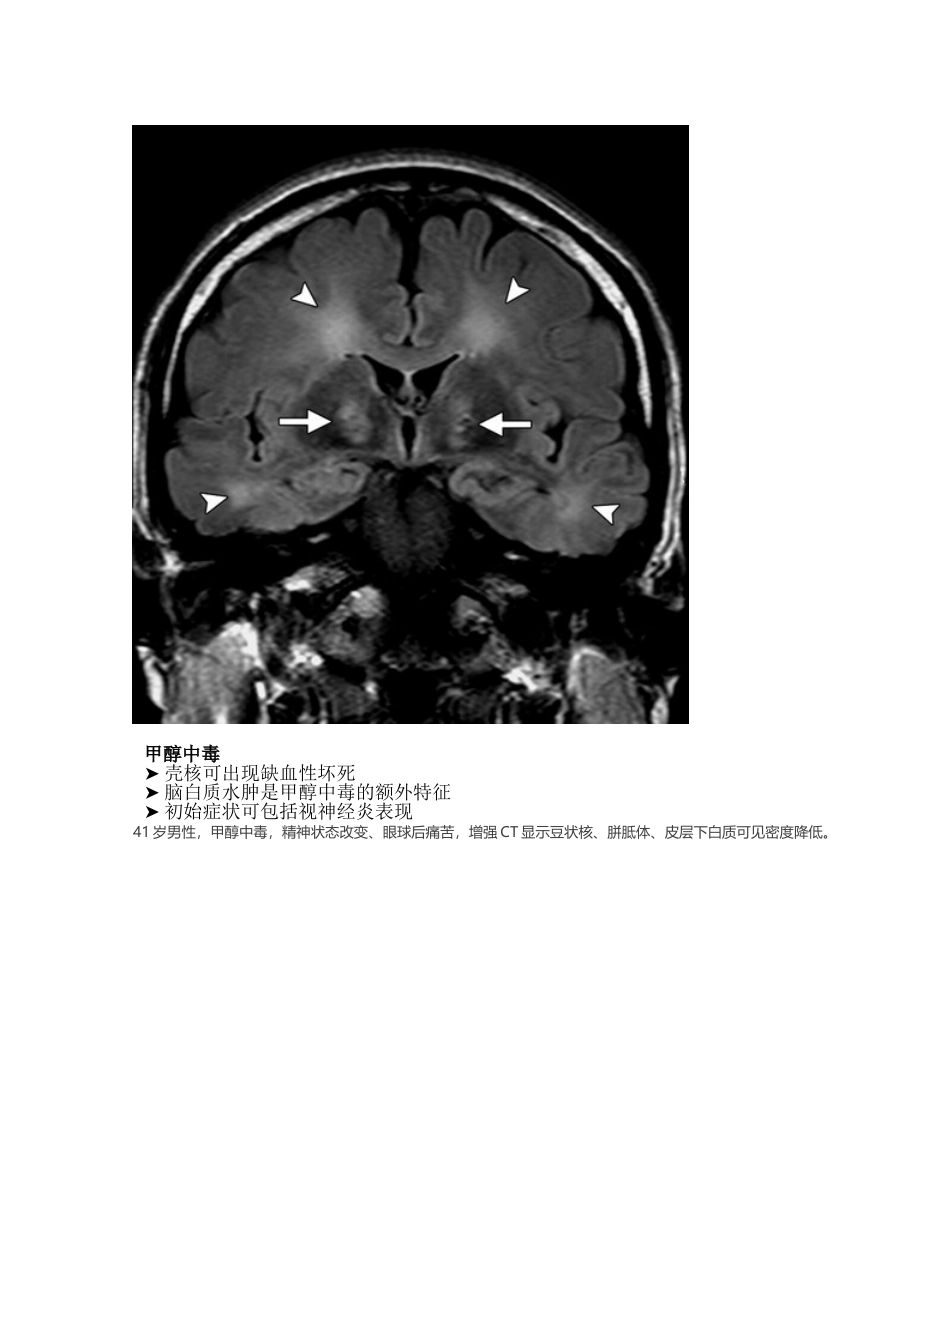

基底节区域异常的疾病逐一鉴别2025-07-08 来源:医脉通 许多种疾病都可表现为基底节和丘脑的异常,包括中毒、全身代谢性疾病、某些退行性疾病、血管异常等。本文将对不同疾病的表现特征进行介绍。进入正文之前,先来复习一下基底节区域的解剖吧:基底节的功能很复杂。这些结构主要涉及运动的产生,并且是锥体外系运动系统的一部分,同时也可以参加记忆、情绪和其他认知功能。由于壳核和苍白球富含线粒体、血管供应和神经递质,且代谢活性高、葡萄糖和氧的利用更多,因此易受代谢异常和许多全身性疾病的影响。丘脑则是由多个核团组成,负责感觉和运动信号的中继,参加意识、睡眠和警觉性的调节。因此,丘脑病变常常导致意识障碍和感觉异常。话不多说,马上进入正题——引起基底节及丘脑异常改变的疾病都有哪些?毒物中毒一氧化碳中毒➤ 表现为意外暴露或自杀未遂后急性认知障碍或昏迷➤ 具有苍白球受累倾向➤ 可能出现 T1WI 短信号和延迟脑白质病➤ DWI 上呈弥散受限33 岁男性,一氧化碳中毒后 4 周,轴位 T2WI 和冠状位 FLAIR 像显示双侧苍白球对称性高信号灶。深部白质对称性高信号区域与延迟性白质脑病表现一致。甲醇中毒➤ 壳核可出现缺血性坏死➤ 脑白质水肿是甲醇中毒的额外特征➤ 初始症状可包括视神经炎表现41 岁男性,甲醇中毒,精神状态改变、眼球后痛苦,增强 CT 显示豆状核、胼胝体、皮层下白质可见密度降低。肝脏疾病➤ 含氮废物通过血脑屏障造成长期毒性脑损伤➤ 锰沉积导致 T1WI 上苍白球、黑质高信号➤ 急性高氨血症可导致双侧基底节、岛叶皮质、扣带回水肿、T2WI 长信号和弥散受限➤ 肝移植后影像学改变可逆55 岁男性,肝硬化,T1WI 上可见双侧苍白球高信号。70 岁男性,急性高氨血症,肝硬化急性失代偿性肝功能衰竭,精神状态改变。影像学检查显示尾状核头、豆状核、岛叶皮质水肿、T2WI 高信号、DWI 弥散受限。非酮症性高血糖➤ 见于糖尿病控制不佳的患者,预后通常较好➤ 主要表现为急性舞蹈病症状、单侧抽搐、精神状态改变➤ CT 常表现为双侧(罕见单侧)苍白球或尾状核高密度➤ MRI 上表现为 T1WI 高信号,T2WI 多变信号68 岁女性,为未经控制的糖尿病患者,出现非酮症性高血糖,表现为舞蹈样症状发作。轴位 T1WI 显示双侧苍白球高信号。低血糖➤ T2WI 上可见双侧大脑皮层、海马、基底节长信号➤ 轻度低血糖表现为 MRI 上一过性白质异常,包括胼胝体压部、内囊和放射冠➤...